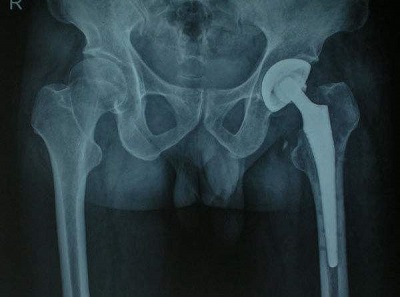

郝召霞主任介绍,股骨头坏死的治疗中西医治疗方法不同,西医治疗股骨头坏死的方法主要有两种:一是药物治疗,包括口服止痛药、抑制骨吸收药物、降胆固醇药物等西药,但是这类药物一般只能起到缓解症状的作用,并不能达到治愈的效果。另外一种就是手术治疗,包括髓心减压术、腓骨移植术等保髋手术,以及临床上常用的股骨头置换手术。

首先,置换手术费用高,对于经济条件有限的家庭存在很大的限制性;其次,术后容易出现并发症,例如:术后疼痛、假体断裂、感染等等;再次,置换的股骨头是有一定的使用年限的,并不是终身,到了一定的时间就必须要再次更换,或二次翻修,一般是在15年左右,这就给患者又带来二次伤害。

所以,选择置换手术往往是年龄比较大和股骨头坏死完全塌陷的患者逼不得已的选择。对于不到60岁的患者而言,还是建议保守治疗。